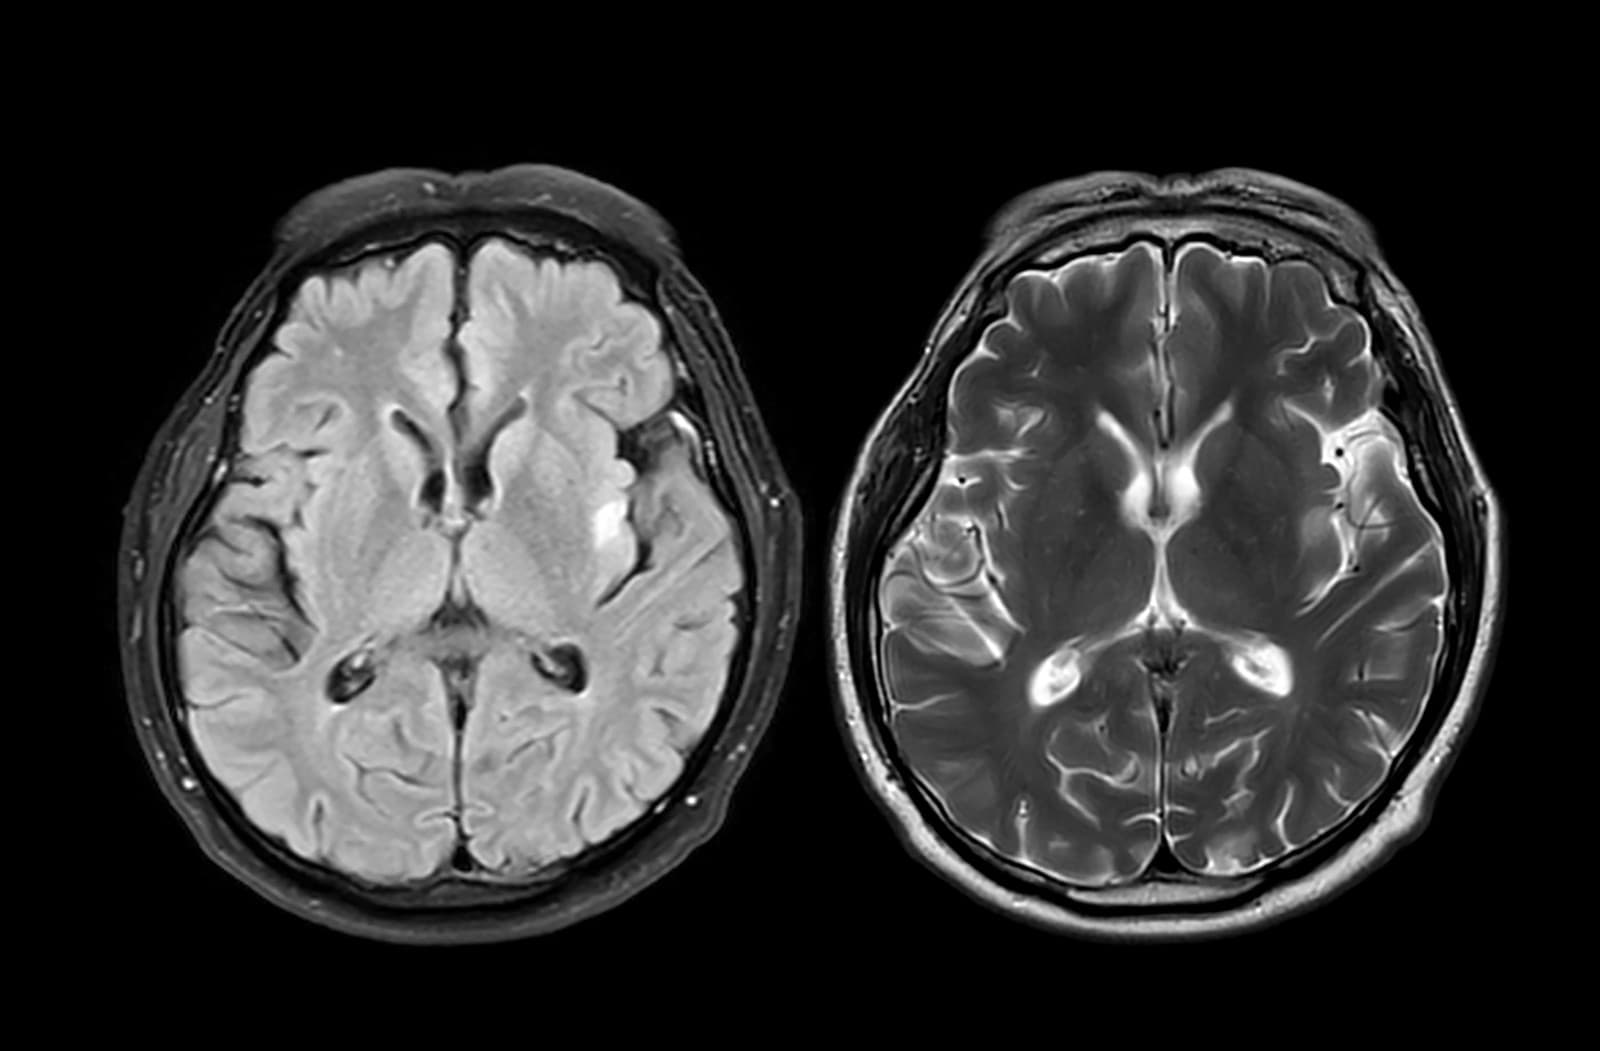

Mnohí vnímajú trasenie rúk ako typický varovný príznak Parkinsonovej choroby. Lekári však upozorňujú, že iné, jemnejšie príznaky, sa môžu objaviť dávno predtým, ako sa u pacientov prejavia akékoľvek poruchy pohybu. Ako informuje Daily Mail, v skutočnosti nie je pokojový tras nevyhnutný na stanovenie diagnózy. Prekvapivo až jeden z piatich pacientov s Parkinsonovou chorobou ho vôbec nemá. Táto jedna z najčastejších neurologických porúch na svete vzniká v dôsledku úbytku nervových buniek v oblasti mozgu zodpovednej za tvorbu dopamínu, čiže látky, ktorá pomáha koordinovať pohyby tela.

Jej nedostatok vedie k problémom, ako sú tras, pády a poruchy pohyblivosti. Ochorenie sa postupne zhoršuje, keď odumiera viac buniek, a pacienti môžu mať časom problém zvládať bežné denné činnosti. Na Parkinsonovu chorobu zatiaľ neexistuje liek, no príznaky sa dajú zmierňovať kombináciou prípravkov a fyzioterapie. Odborníci pripomínajú, že čím skôr sa ochorenie diagnostikuje, tým skôr má pacient prístup k liečbe, ktorá môže výrazne zlepšiť kvalitu života. Neurológovia pri stanovení diagnózy zvyčajne sledujú typické pohybové príznaky, ako sú spomalenosť, stuhnutosť a pokojový tras.

Iné, nepohybové príznaky sa však môžu u pacientov prejaviť skôr, aj o viac ako desať rokov. Tieto prejavy sa objavujú v skorom, tzv. prodromálnom štádiu ochorenia a signalizujú jeho pomalý nástup. V období, keď sa začnú prejavovať typické motorické príznaky, môže byť podľa lekárov až 70 percent nervových buniek v časti mozgového kmeňa zodpovednej za vôľové pohyby už odumretých buniek. Avšak nie každý človek s týmito skorými príznakmi ochorie na Parkinsonovu chorobu. Výskum ale naznačuje, že u niektorých ľudí môžu byť prvým varovným signálom. Na čo by sme si teda mali dávať pozor?

U niektorých môže viesť k zmene hmotnosti, keďže necítia jedlo a u iných ovplyvňuje náladu. Strata čuchu môže byť mierna alebo úplná a prináša aj bezpečnostné riziká, napríklad neschopnosť zacítiť dym. Vedci sa domnievajú, že súvisí so zmenšením čuchového laloku mozgu. U pacientov sa v tejto oblasti hromadí proteín alfa-synukleín, ktorý sa za normálnych okolností nachádza v bunkách produkujúcich dopamín. Pri Parkinsonovej chorobe sa tieto proteíny zhlukujú a vytvárajú usadeniny, ktoré sa šíria mozgom.